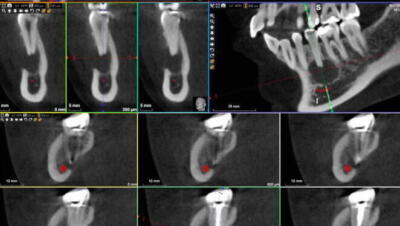

Het Belang van Röntgenfoto's in Endodontie: Essentiële Inzichten voor Tandheelkundige Zorg

AI in Endodontie: Verbeterde Nauwkeurigheid voor Optimale Behandelingen